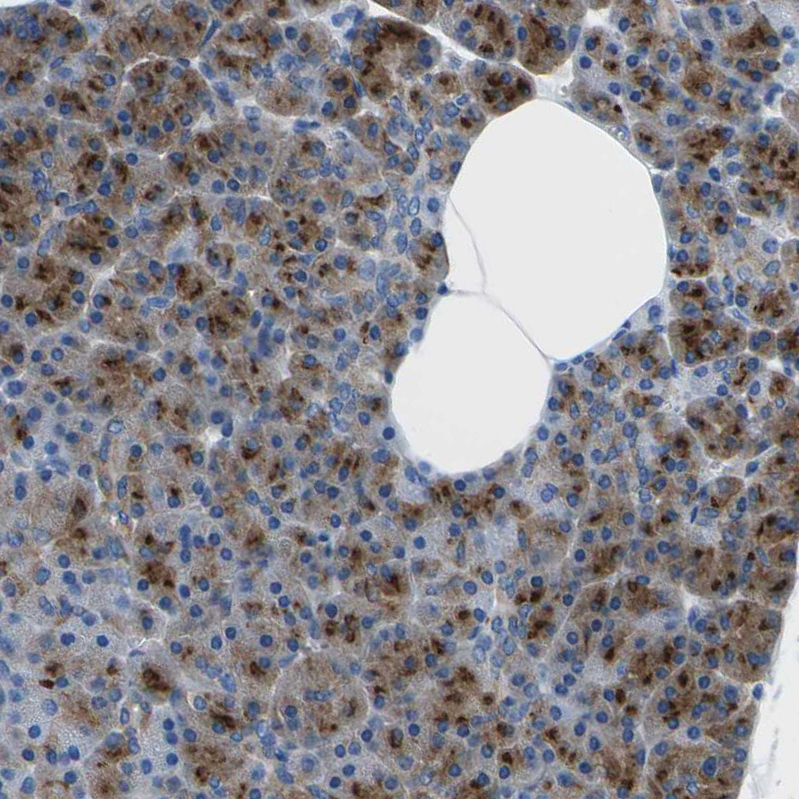

Immunohistochemical staining of human pancreas shows strong cytoplasmic positivity in exocrine glandular cells.